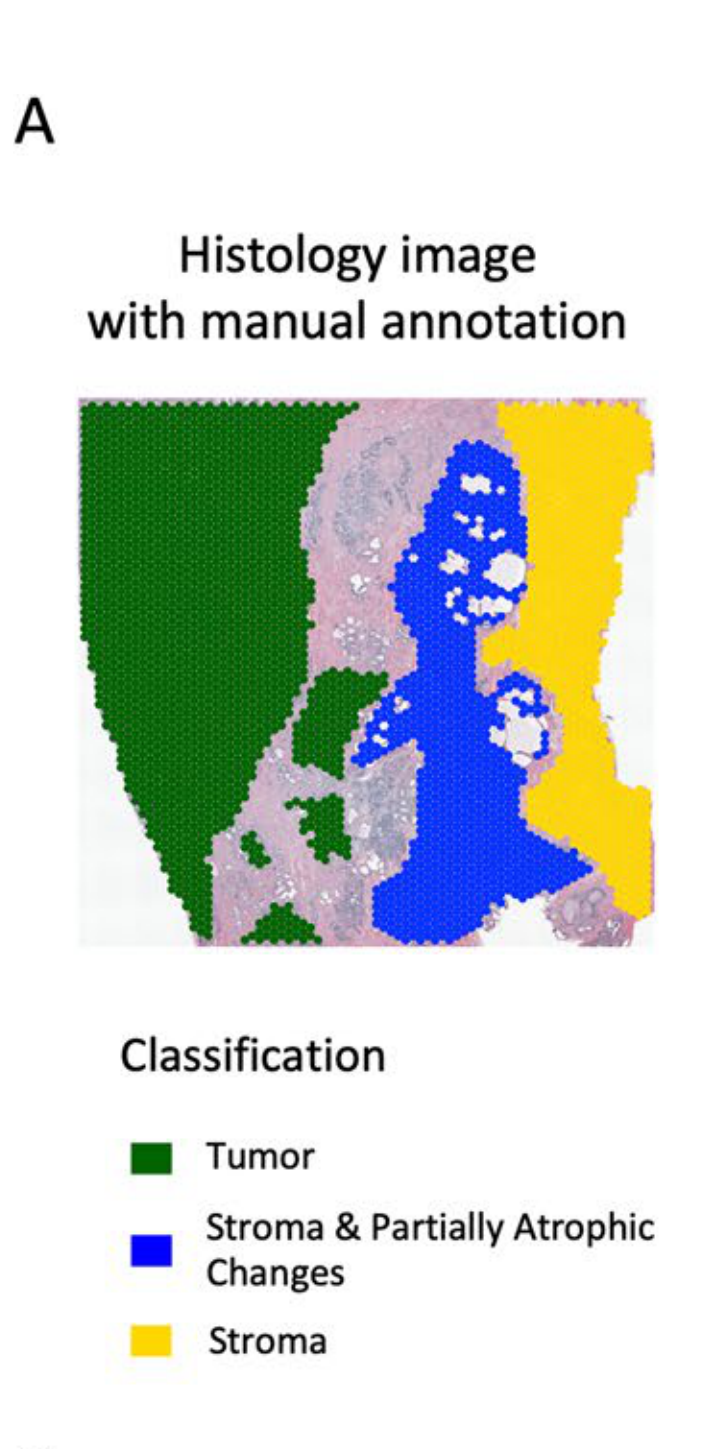

Zhou Q. et al. - 2025

Path-MGCN: a pathway activity-based multi-view graph convolutional network for determining spatial domains

Condition Dimension

N/A

Data Components

Gene Expression Matrix

Data

Modality

Sequencing-based

Resolution of observation

Multi-cellular

Visualized Elements

Observation

How does the computational method identify cancer tissue heterogeneity?

Biological

Tissue

Abstraction

Partial

Chart Type

Hexplot

Communicative/Contextualization

Annotation

Comparative Design

Juxtaposition : Small multiples

Layout

Spatial : Physical

Scalability Strategy

None (Item-level)